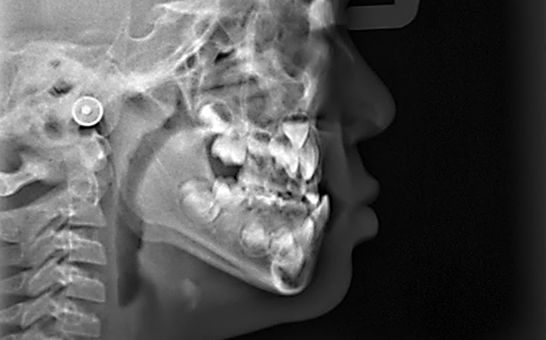

디지털 기반의 시뮬레이션 진단 과정을 통해 치아의 배열, 턱 관절 상태,

교합 상태를 정밀히 분석 후 교정 치료 계획을 수립하여 복잡한 케이스,

어려운 고난도 케이스도 전문적인 교정 치료가 가능합니다.

※ 바른선택치과의원은 의료법을 준수하며 위 케이스는 실제 내원 환자분의 동의하에 공개된 사진과 동일한 환자분께 같은 조건에서 촬영한 사진을 활용했습니다.

개인에 따라 진료 및 치료 방법이 다르게 적용할 수 있으며, 효과와 부작용이 개인마다 다르게 나타날 수 있는 점을 안내해 드리며, 진료 전 전문의료진과 충분한 상담을 권해드립니다.